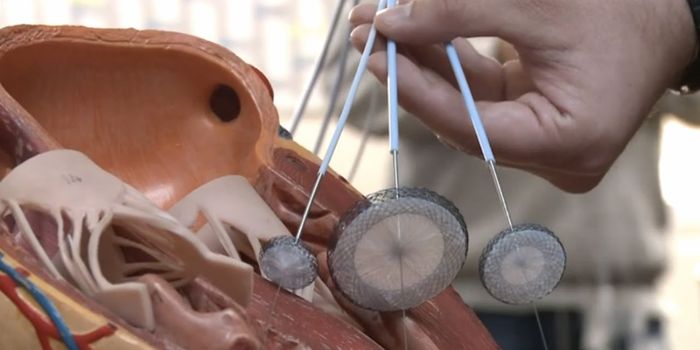

OCT 17, 2017VideosWhen a stroke occurs, the brain can be severely damaged. There are two kinds of strokes, an ischemic stroke where a bloo ...